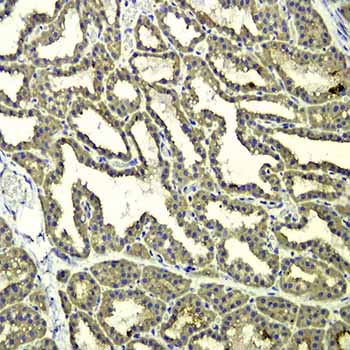

免疫组织化学又称免疫细胞化学,可以用于:(1)显色剂标记的特异性抗体在组织细胞原位通过抗原抗体反应和组织化学的呈色反应;(2)是对相应抗原进行定性、定位、定量测定的一项新技术。

免疫组织化学又称免疫细胞化学,是指带显色剂标记的特异性抗体在组织细胞原位通过抗原抗体反应和组织化学的呈色反应,对相应炕原进行定性、定位、定量测定的一项新技术。

它把免疫反应的特异性、组织化学的可见性巧妙地结合起来,借助显微镜( 包括荧光显微镜、电子显微镜) 的显像和放大作用,在细胞、亚细胞水平检测各种抗原物质( 如蛋白质、多肽、酶、激素、病原体以及受体等) 。

二,免疫组化技术的基本原理

免疫组化技术是一种综合定性、定位和定量;形态、机能和代谢密切结合为一体的研究和检测技术。在原位检测出病原的同时,还能观察到组织病变与该病原的关系,确认受染细胞类型,从而有助于了解疾病的发病机理和病理过程。

免疫酶组化技术是通过共价键将酶连接在抗体上,制成酶标抗体,再借酶对底物的特异催化作用,生成有色的不溶性产物或具有一定电子密度的颗粒,于普通显微镜或电镜下进行细胞表面及细胞内各种抗原成分的定位。